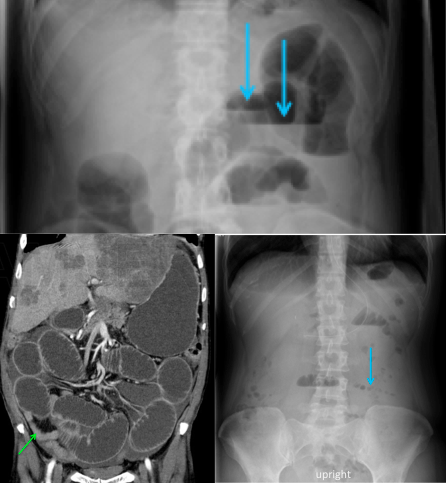

Blockage of flow of fluid or air within a lumen channel (can happen anywhere in the GI, biliary system, pancreatic duct, etc); numerous etiologies (strictures, adhesions, stones)

Normal small bowel diameter: < 2.5cm transverse diameter

Upstream of obstruction - lumen dilates; usually presence of air-fluid levels (may show up as a string of pearls sign (air trapped in plica circularis))

Downstream of obstruction – lumen decompresses as normal flow of fluid/air evacuates the lumen distal to the obstruction

Use Radiography or CT

Supine - Dilated small & large bowel on supine image

Upright - Air fluid levels in small & large bowels and colon (can only be seen on upright and lateral decubitus (not on supine))